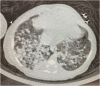

Figure 1:

CT scan lungs and airways of the infant, showing diffuse nodular parenchymal opacities bilaterally, most significantly involving the right hemithorax September 2020.